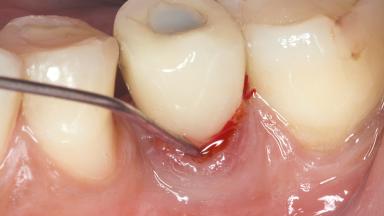

Peri-Implant Mucositis Treatment Outcomes on an Implant with a Submucosal Restoration Margin

Mauricio Araujo and Flauvia Matarazzo present this straightforward clinical case, demonstrating the potential effect of implant placement depth on the resolution of peri-implant treatment. A 42-year-old systemically healthy female patient, a non-smoker with no history of periodontitis, was treated at the Dental Clinic at the State University of Maringá, Brazil between 2008 and 2009, when she received five implants restored with single crowns at sites 14, 26, 27, 36, and 46. After delivery of the implant-supported prosthetic restorations, the patient was enrolled in the supportive peri-implant therapy (SPiT) maintenance program at the same university.